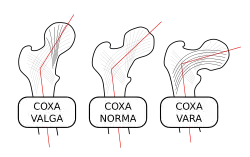

Alternation of trabecular pattern in the thigh bone reflects mechanical stress | |